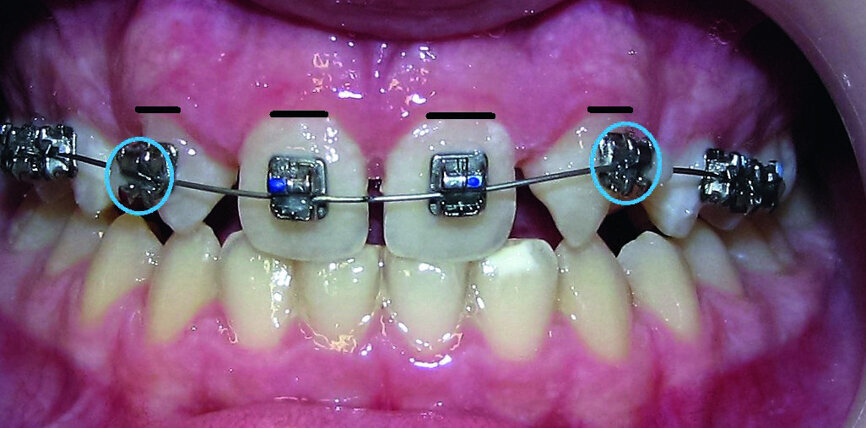

- Upper bracket placement (Fig. 22): level and align the gingival margins, and correct the torque on the upper canines who will substitute the lateral incisors.

- Implants space opening: substitute laterals with canines (Figs. 23–25) and substitute canines with first premolars (Figs. 26–28).